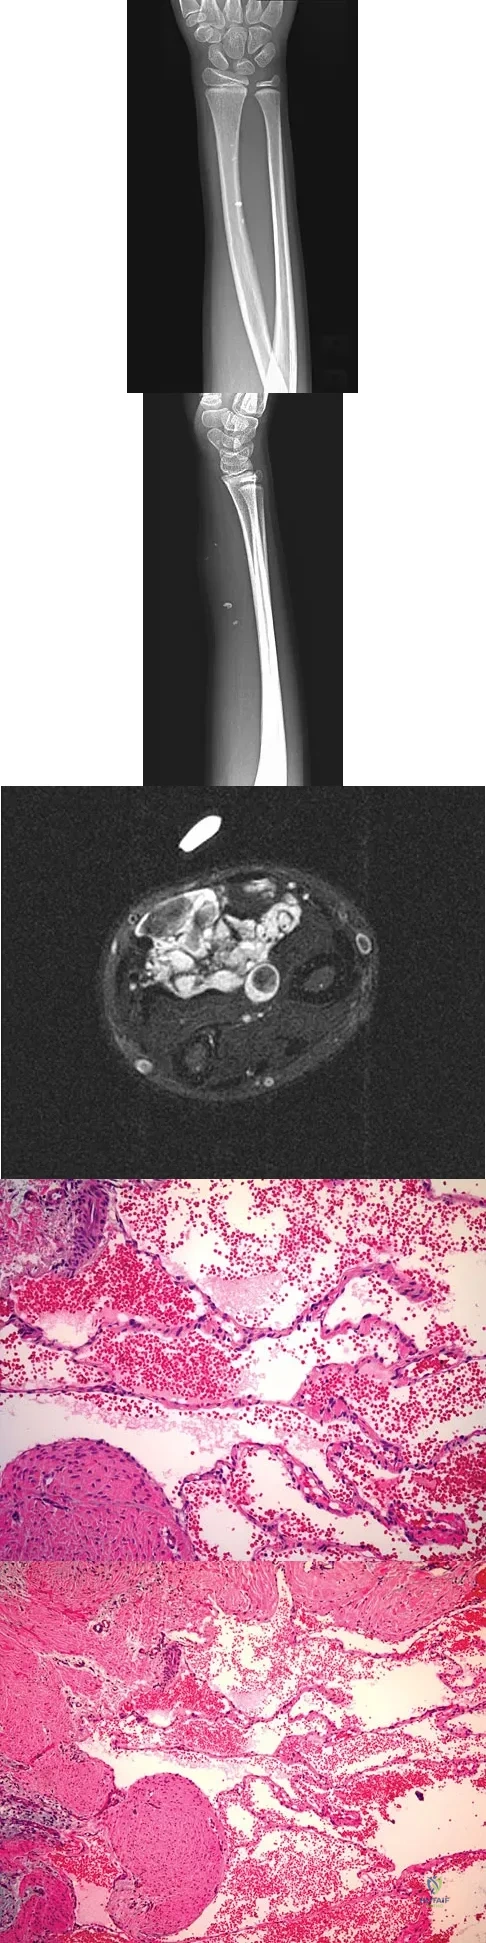

A 7-year-old girl has had a painful forearm for the past 2 months. Examination reveals fullness on the volar aspect of the forearm. Radiographs and an MRI scan are shown in Figures 42a through 42c. Biopsy specimens are shown in Figures 42d and 42e. What is the most likely diagnosis?

Explanation

A 16-year-old girl has had painless swelling in her posterior left arm for the past 4 months. A radiograph, MRI scans, and an incisional biopsy specimen are shown in Figures 43a through 43d. What is the cytogenetic translocation most commonly associated with this tumor?

Explanation

A 20-year-old woman has had wrist pain for the past 5 months. A radiograph, MRI scans, and biopsy specimen are shown in Figures 46a through 46d. The patient is then treated with intralesional surgery. The patient should be counseled that her risk of developing lung metastasis is approximately what percent?

Explanation